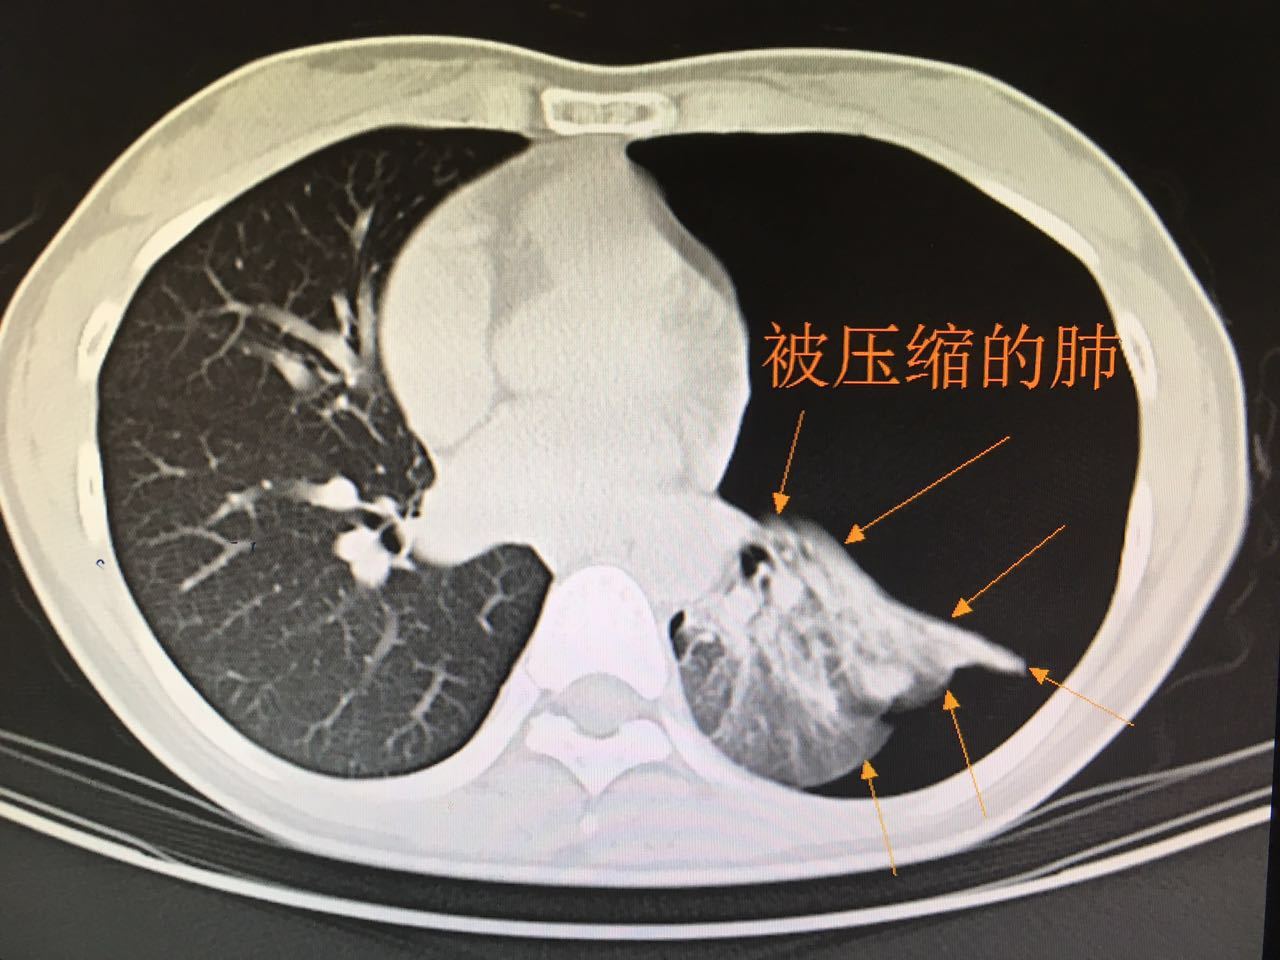

外科治疗闭合性气胸危重病人一例

(一)闭合性(单纯性)气胸根据脏层胸膜破口的情况和气胸发生后对胸膜腔